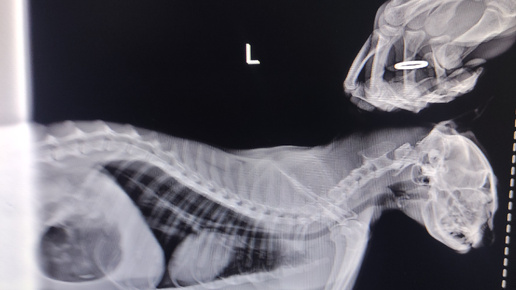

Симбе очень плохо/Абиссинская кошка сбитая машиной/Делаю рентген Симбе/Ветеринарные клиники НИКА и ВЕТЕРИНАР/Катаюсь с котом на такси